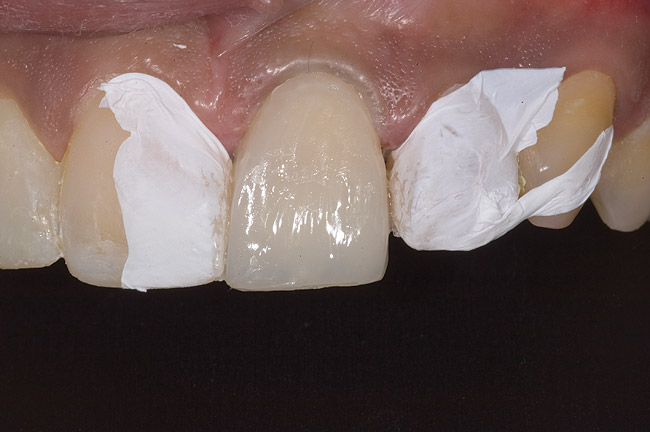

Figure 9: Tooth No. 9 minimally prepared for resin layering on the labial surface.

Figure 9

Figure 10  Tooth No. 9 with no preparation on the palatal surface to restore lost form with bonding resin.

Figure 10

During the next appointment, a palatal index of the approved provisional was fabricated with putty silicone. This enabled the clinician to precisely build the lingual surfaces and incisal edges of teeth Nos. 6 through 11. The provisional mock-up resin on No. 9 was removed, and the underlying labial tooth was roughened with an abrasive diamond bur. No tooth structure was removed from the palatal surface, and unsupported enamel was rounded off from the labial. An ultrathin dry cord was placed in the gingival sulcus on No. 9 (Figure 9 and Figure 10). Teflon tape was used to isolate No. 9 from adjacent teeth. Then 37% phosphoric acid was used to totally etch the labial surface for 10 seconds and the palatal surfaces on No. 9 for 5 seconds. Single bond was applied and spread uniformly across the tooth and light-cured for 20 seconds.